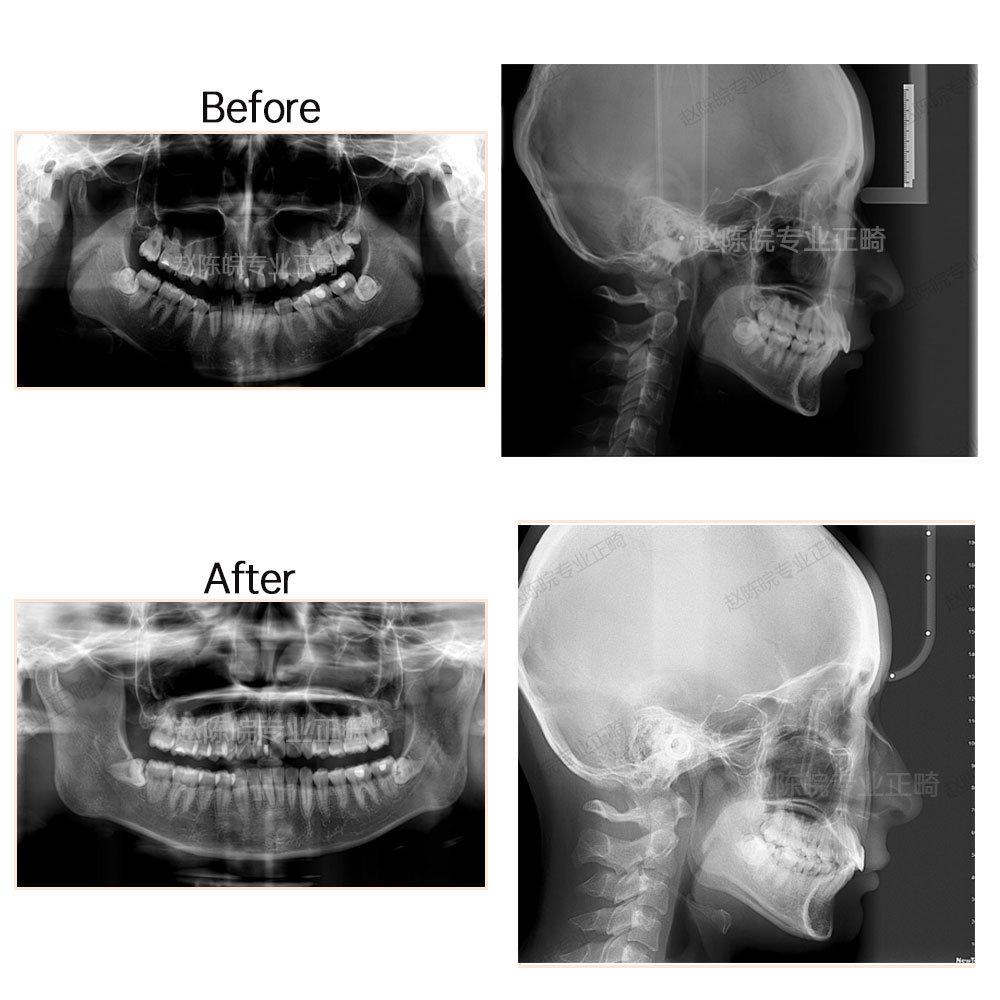

?矯正前后X線片前后對(duì)比圖(觀察對(duì)比側(cè)面顱骨情況及牙體牙周情況)

測(cè)量分析模型分析:上頜擁擠度3.5mm,下頜擁擠度3.5mm,前牙bolton比81.6%,spee曲線3.8mm

診斷:安氏2類,骨性2類錯(cuò)頜

上頜推磨牙向后加適量片切,內(nèi)收前牙,糾正上中線;下頜擴(kuò)弓加前牙適量片切排齊牙列,壓低下前牙整平spee曲線。

完成結(jié)果:達(dá)到矯治目標(biāo),牙列排齊,中線就真正,咬合中性,覆合覆蓋正常。